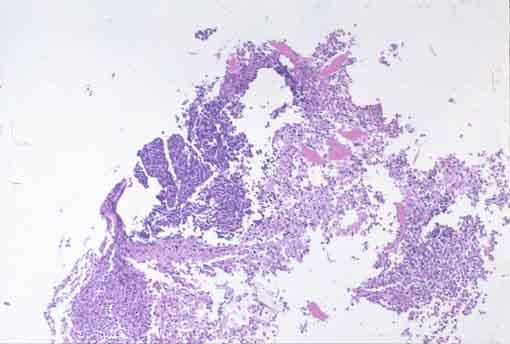

질환(병리주체)의 분류 악성 상피성종양/미분화암

부위(장기별) 식도/2개 이상

검사방법 마이크로

종양의 육안분류 5형(분류불능)/

종양의 최대경(밀리미터) 40이상